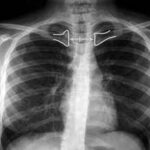

La clavícula es un hueso largo y delgado situado en la parte superior y frontal del tórax humano, extendiéndose desde el manubrio esternal hasta el acromion de la escápula. Su…